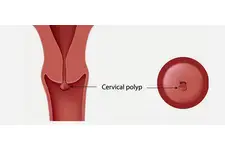

Ses telleri, sesin üretilmesinde kritik bir rol oynayan ve larenks içerisinde yer alan iki kaslı yapıdır. Bu yapılar, çeşitli etkenler sonucunda tahriş olabilir ve bu tahrişin sonucunda ses tellerinde polip oluşumu meydana gelebilir. Polipler, ses tellerinin yüzeyinde oluşan benign (iyi huylu) tümörlerdir ve genellikle ses kalitesini olumsuz yönde etkiler. Bu makalede ses tellerinde poliplerin belirtileri ve tedavi yöntemleri ayrıntılı bir şekilde ele alınacaktır. Ses Tellerinde Poliplerin Belirtileri Ses tellerinde polip oluşumunun belirtileri, hastalığın evresine ve poliplerin boyutuna göre değişkenlik gösterebilir. Genel olarak aşağıdaki semptomlar gözlemlenebilir:

Bu belirtiler, poliplerin boyutuna ve sayısına bağlı olarak değişiklik gösterebilir. Eğer bu belirtiler uzun süre devam ediyorsa, bir kulak burun boğaz uzmanına başvurmak önemlidir. Poliplerin Nedenleri Ses tellerinde poliplerin oluşumuna yol açan birçok faktör bulunmaktadır: